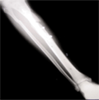

Progress

Excellent return of function and good correction